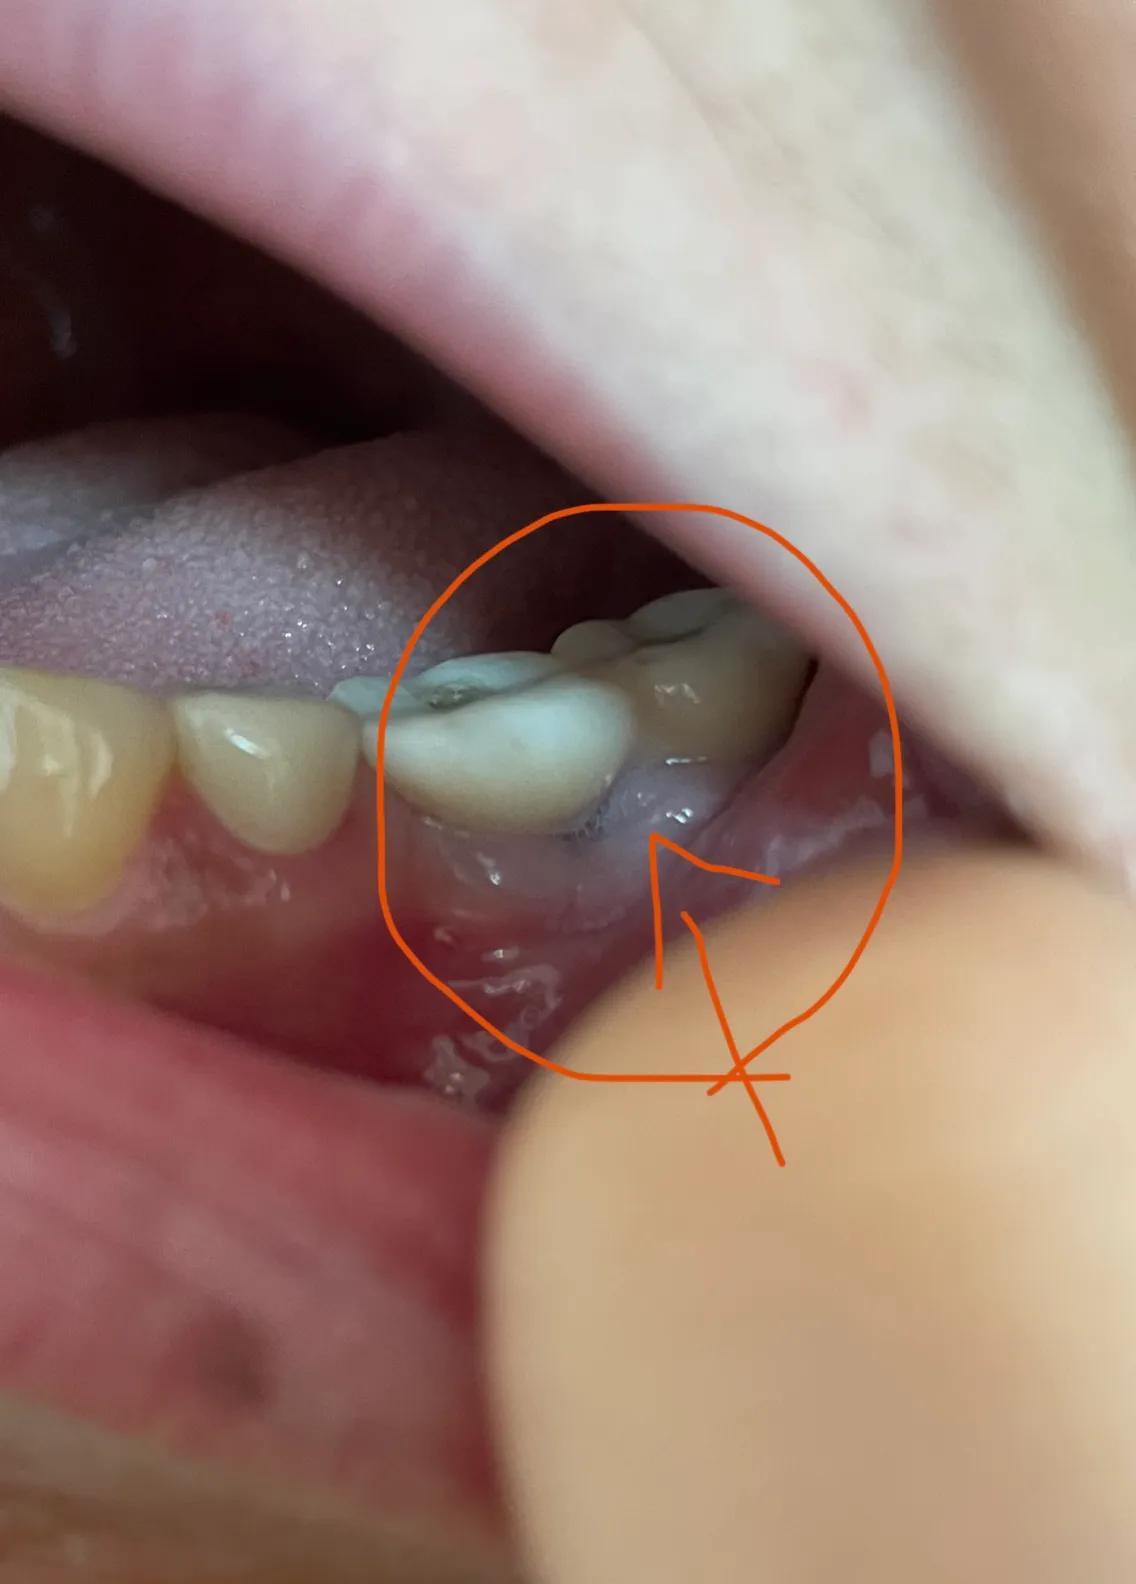

第二副牙帶好 發(fā)現(xiàn)牙齦又缺肉了 更別提貼合牙齒了 而且是一直的疼 一直難受

牙齦是外翻和牙齒分開的 顏色發(fā)白 和其他部位牙齦不是一樣顏色

我不是專業(yè)醫(yī)生 不懂他們所說的正?,F(xiàn)象都包括什么 要怎么后期維護(hù) 我現(xiàn)在先不講看不見的難受 疼 先講直觀能看見的 他們哪位醫(yī)生可以做到把大米粒塞到牙齒下面 和將近半厘米的塑料條塞過他們的牙齒 吃過東西就要用沖牙器 不然隔頓就臭了

沒辦法自己又出去拍片子 找原因 看了幾家醫(yī)院 才知道連種植體也種偏了 牙冠也沒有就位………